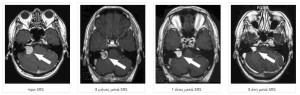

Ακουστικά Νευρινώματα

To ακουστικό νευρίνωμα αποτελεί καλοήθη όγκο που προέρχεται από νευρικά κύτταρα της όγδοης κρανιακής συζυγίας που σχετίζεται με την ακοή και τη διατήρηση της ισορροπίας.

Αποτελεί όγκο που εξελίσσεται βραδέως προκαλώντας συμπτώματα όταν αυξηθεί αρκετά σε μέγεθος όπως οι εμβοές, η απώλεια ακοής, και οι διαταραχές στην ισορροπία.

Τα ακουστικά νευρινωματα, αν και καλοήθεις και βραδέως αναπτυσσόμενοι όγκοι λόγω της δύσκολης χειρουργικής προσπέλασης τους εξαιτίας της περιοχής που βρίσκονται- αλλά και την άμεση σχέση τους με το προσωπικό νεύρο, το ακουστικό νεύρο και το εγκεφαλικό στέλεχος αποτελούν μία από τις δυσκολότερες νευροχειρουργικές επεμβάσεις.